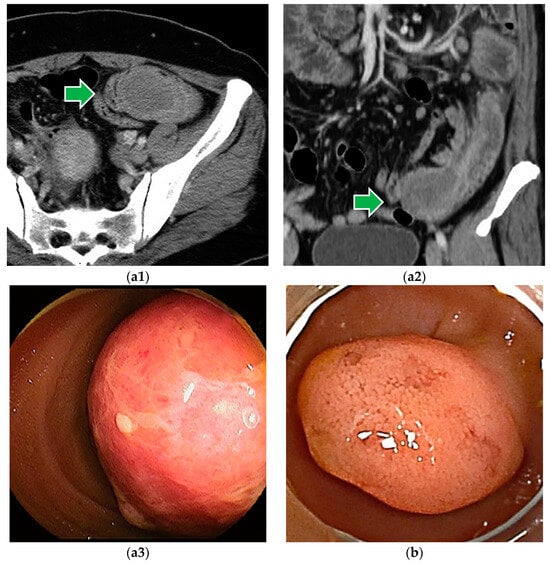

Figure 4.

Neuroendocrine tumor: (a) SMT-like lesion with atrophied surface villi and dilated capillaries (b) A high-grade lesion with ulcers on the surface.

The endoscopic image of NET is yellowish SMT-like, but it is precisely a tumor of epithelial origin. It is often seen as an elastic, hard, mobile tumor with atrophied surface villi and dilated capillaries (Figure 4a). Depressions, ulcers, or erosions on the surface may indicate a high-grade lesion (Figure 4b).